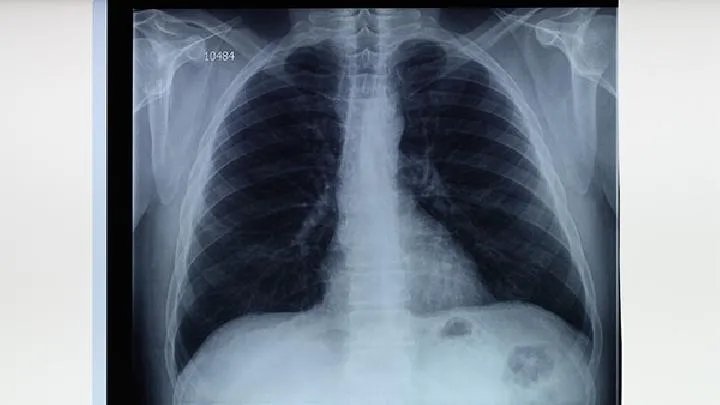

肺结核是可以根治的,但是我们要有调理的进行治疗,否则的话是很难治愈的。临床上对于肺结核的治疗有初、复治之分,病人有排菌和不排菌之别,结核菌有处于繁殖生长期和休眠静止期之别。抗痨药物有作用于酸性环境和细胞内酸性环境的药物,还有作用细菌外得碱性或中性环境的药物,一个合理正规的化疗方案必然有二种或二种以上的杀菌药,合理的剂量、科学的用药方法,足够的疗程,还要规律、早期用药,才能治愈。